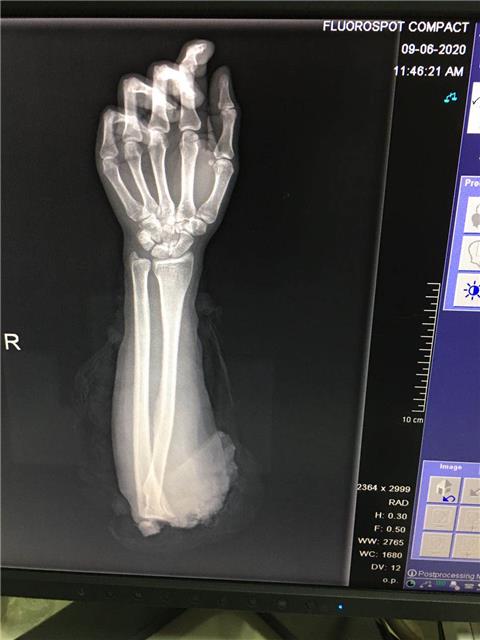

2020年6月9日8时左右,张女士刚开工,见机器有物体堵塞,伸手进入机器中修理,丈夫不小心启动机器时,致张女士右肘关节处完全离断,由120送至当地医院紧急处理后转送至贵航三OO医院骨一科。

经诊查,该病人存在右肘部完全性离断伤,伤情严重,情况危急,随时可能有生命危险。骨一科立即组织人员抢救,成立以科主任田广为首的抢救小组,针对病人伤情严重,断肢再植后不能存活的可能,抢救小组认真制定救治方案。

在麻醉科的配合下,张女士的手术由田广医生亲手操刀,任永和、欧阳东医师配合,通过大面积清创,依次固定骨折,吻合血管、肌腱及神经,经过6个小时的抢救,手术最终成功,离断患肢血运良好,目前张女士正在康复治疗中。

田广表示,张女士来院时断臂右肘关节完全离断,因大肢体的肌肉组织多,若超过6至8小时没能通过手术接上,便会出现不可逆的坏死。

“张女士送到医院时情况很不好,血色素6克。庆幸的是,断肢前期被当地医院做了很好的冷藏处理,医院输血科也经过多番努力找来1600ML的血液,手术终获成功。”